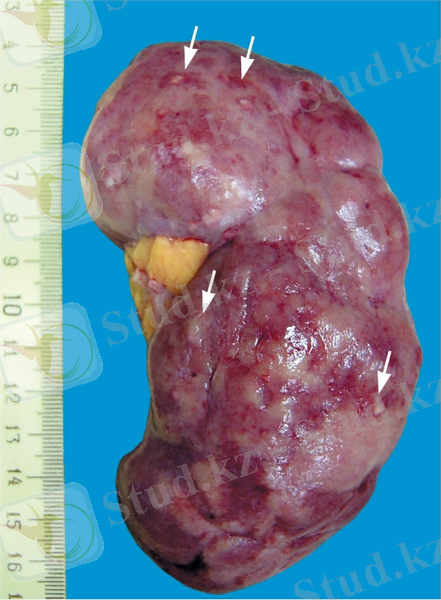

4. Макропрепараттар (a, б) . Көкбауырдың цианозды индурациясы: көкбауыр үлкейген, тығыз консистенциялы (индурация), беті тегіс, капсула шиеленіскен, тегіс, көкбауыр ұлпасы кесілген жерінде цианозды. (цианотикалық) ; а - «глазурленген» көкбауыр - көкбауыр капсуласының гиалинозы және оның цианотикалық индурациясы.